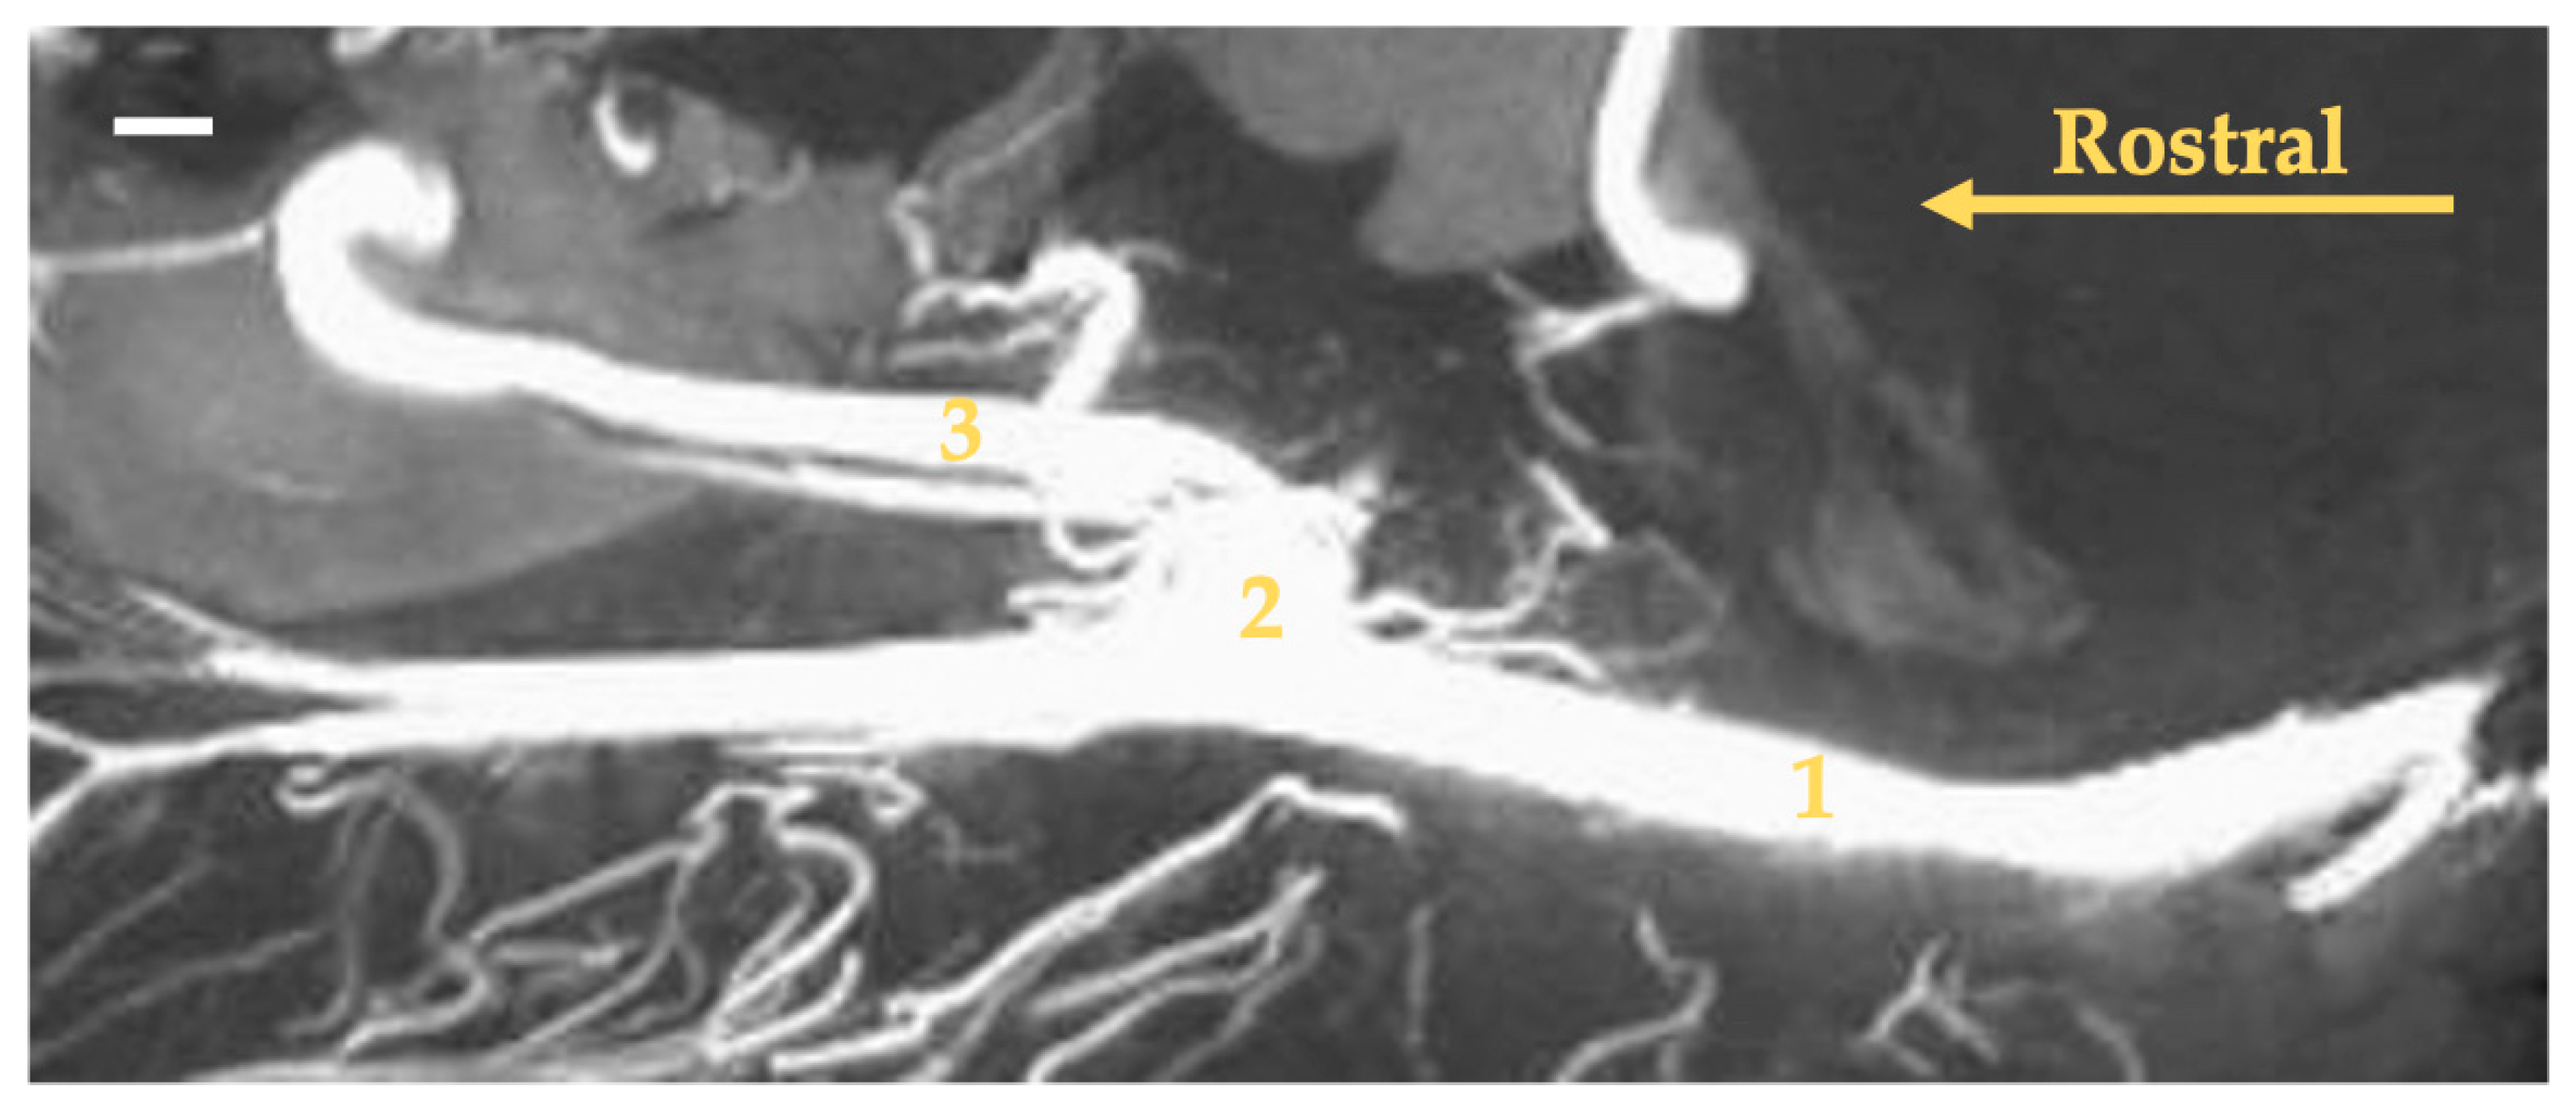

3. Results